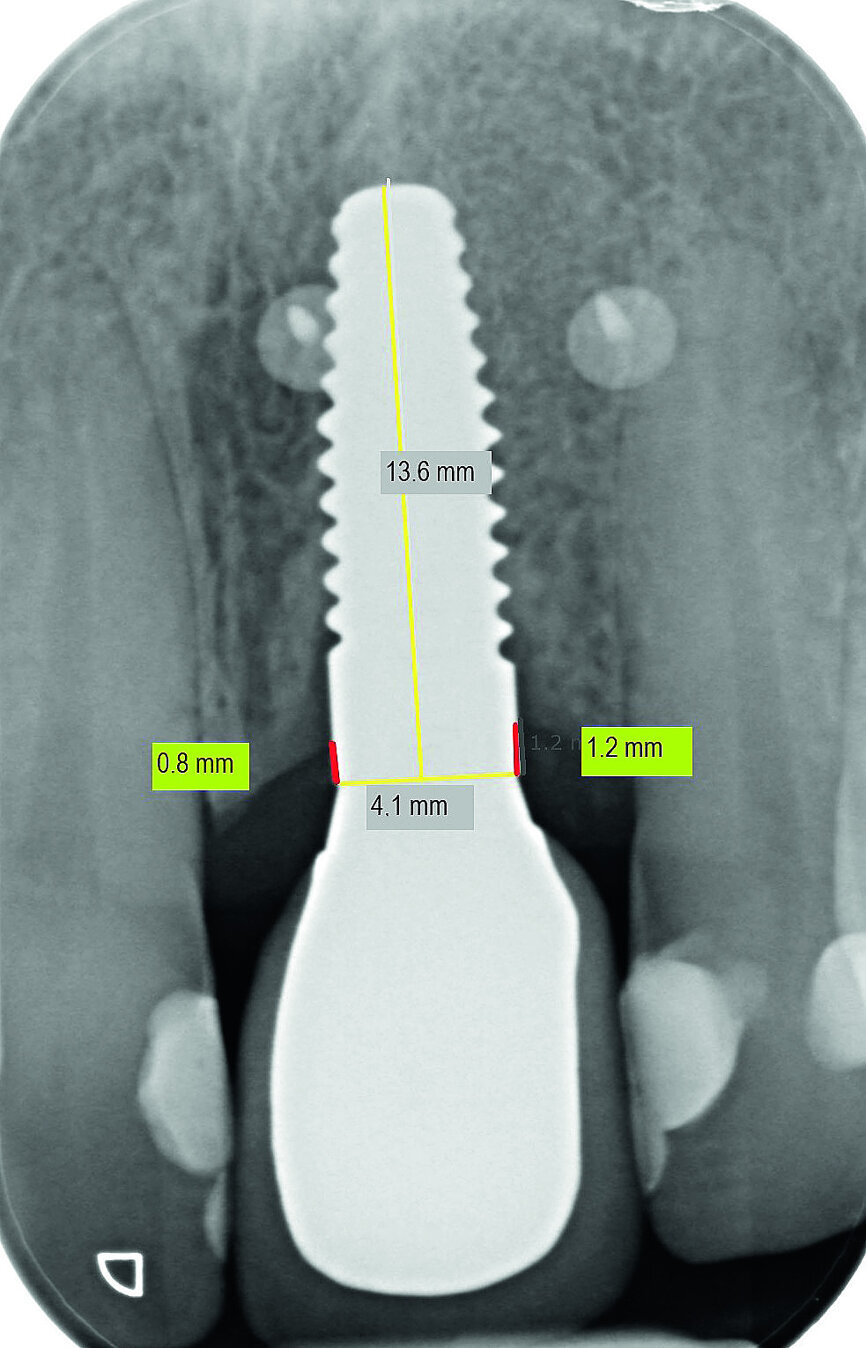

Fig. 13b: Bone resorption was detected after six months and bone gain after 12 months. The yellow line represents the actual implant length (13.6mm). The red lines indicate the mesial and distal distances from the top of the implant to the first bone contact.

Fig. 13c: Bone resorption was detected after six months and bone gain after 12 months. The yellow line represents the actual implant length (13.6mm). The red lines indicate the mesial and distal distances from the top of the implant to the first bone contact.

Bone resorption was detected six months after exposure (mesial bone: 0.6 mm; distal bone: 0.4 mm), and a gain of bone was observed 12 months after exposure (mesial bone: 0.0 mm; distal bone: 0.3 mm; Figs. 13a–c). In accordance with the findings in the relevant literature, bone resorption in our patient was the greatest in the first six months.16 However, the literature findings are in reference to one-piece ceramic implants, in contrast to the two-piece implant system used in this case. This phenomenon of bone resorption is a relatively rare occurrence in implantology and should be confirmed by evidence-based long-term studies before a definitive conclusion can be drawn. Evaluations are in progress.